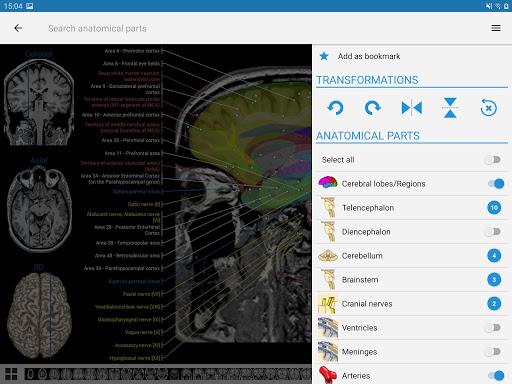

IMAIOS e-Anatomy adalah atlas anatomi manusia untuk dokter, ahli radiologi, mahasiswa kedokteran, dan teknisi radiologi. Dapatkan cuplikan lebih dari 26.000 gambar medis dan anatomi secara gratis sebelum berlangganan atlas anatomi manusia terperinci kami.

e-Anatomy memiliki lebih dari 26.000 gambar yang berisi serangkaian gambar dalam tampilan aksial, koronal, dan sagital serta radiografi, angiografi, gambar diseksi, bagan anatomi, dan ilustrasi. Semua gambar medis diberi label dengan cermat, lebih dari 967.000 label tersedia dalam 12 bahasa termasuk Terminologia Anatomica Latin.

- Pilih label anatomi berdasarkan kategori

- Mudah menemukan struktur anatomi berkat pencarian indeks